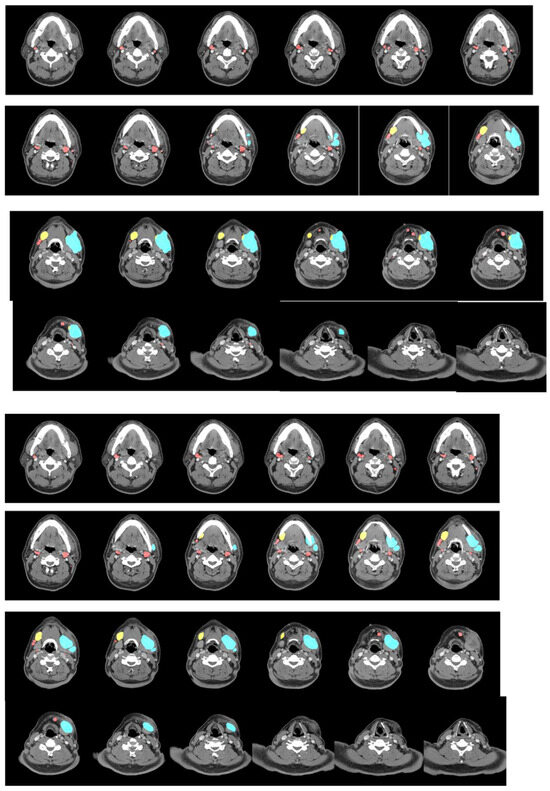

We analyzed lymph nodes detected by the model in the test set to determine the clinical characteristics it may capture. Table 1b shows that, of the 176 identified negative lymph nodes, 167 had a short axis <1 cm. In contrast, all identified positive lymph nodes with ENE had a short axis >1 cm. Figure 2 shows some of the model’s accurate predictions.

Figure 2.

Examples of inference results. (Upper: inference result; middle: ground truth; lower: original image) The inference results compared with ground truth annotation. Red: negative; yellow: positive; light blue: extranodal extension.